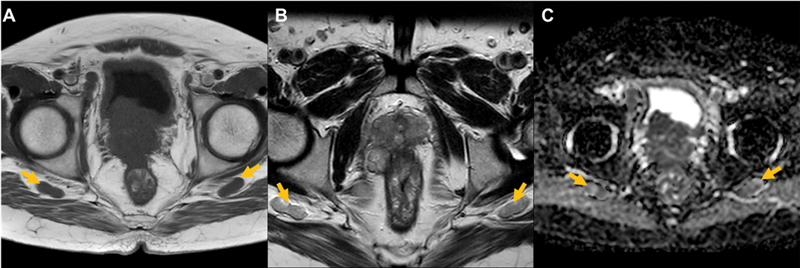

An unusual and unique case of prostate adenocarcinoma with involvement of bilateral inferior gluteal lymph nodes is reported. The patient was a 42-year-old male, with conventional prostatic adenocarcinoma (Gleason score: 5 + 4 = 9), who, during disease progression with rising serum prostate specific antigen levels following medical androgen deprivation therapy, demonstrated new prostate-specific membrane antigen expressing metastatic intermuscular deposits in the bilateral gluteal region, subsequently proven to be bilateral inferior gluteal nodal metastasis. A therapeutic implication to this may be that these nodes usually fall beyond the range covered by the therapeutic radiation field coverage where external radiotherapy is the advocated modality of choice and are not easily reachable through standard surgical procedures. As a result, they could have an impact on the way patients are clinically treated and on their prognosis.

报告了一例不寻常且独特的双侧臀下淋巴结受累的前列腺腺癌病例。患者是一名 42 岁的男性,患有传统的前列腺腺癌(格里森评分:5 + 4 = 9),在接受药物雄激素剥夺治疗后,随着病情的发展,血清前列腺特异性抗原水平不断升高,在双侧臀部区域出现了新的前列腺特异性膜抗原表达的转移性肌间沉积物,随后被证实为双侧臀下淋巴结转移。其治疗意义可能在于,这些结节通常位于治疗放射野覆盖范围之外,而外放射治疗是首选的治疗方式,并且不易通过标准外科手术到达。因此,它们可能会对患者的临床治疗方式和预后产生影响。